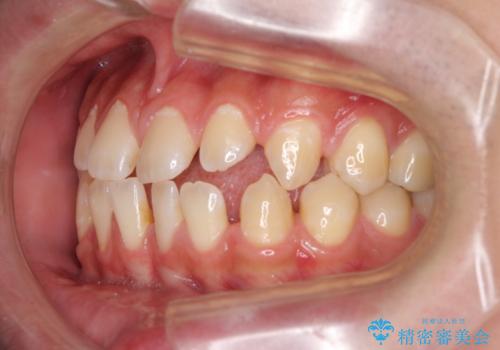

- 上下前歯の隙間を気にして来院された患者様です。

飲み込みや話をするときに舌を突出させる癖が強くあり、それが原因でスペースが空いていました。

舌癖を改善するためのトレーニングを行いながら、ワイヤー装置を用いて前歯の隙間を閉じていくこととしました。